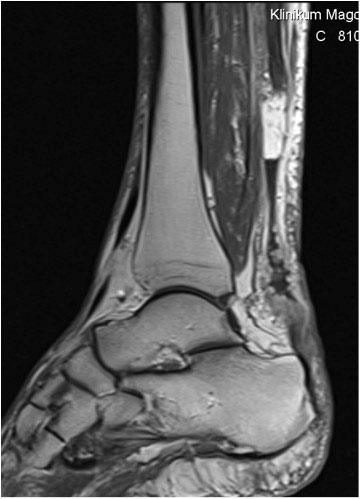

Der geübte Untersucher kann anhand des seitlichen Röntgenbildes die Diagnose einer Achillessehnenruptur stellen. Die Konturen des Kager-Dreiecks – gebildet von der ventralen Begrenzung der Achillessehne, der posterioren Tibiakante und der kranialen Kalkaneuskortikalis – verstreichen im Rupturfall (Kager 1939). Die MRT- Diagnostik spielt für die Primärdiagnostik der frischen Achillessehnenruptur eine untergeordnete Rolle und ist im Normalfall nicht notwendig. Anders verhält es sich bei den chronischen Rupturen. Hier ist die MRT ein wichtiges Diagnostikum insbesondere in Hinblick auf die Beurteilung der Sehnen- und Muskeldegeneration (Abb. 6).

Abbildung 6

Neben der strukturellen Wiederherstellung der Sehne ist die funktionelle Beurteilung des Muskels von entscheidender Bedeutung. Ist es bereits zu einer Degeneration der Muskeln gekommen, kann ein gutes funktionelles Ergebnis, trotz subtiler Sehnenrekonstruktion, nicht erreicht werden. Die Arbeitsgruppe um Hoffmann et al. 13 konnte in ihrer Arbeit zeigen, das es - ähnlich wie bei Patienten mit chronischen Supraspinatusrupturen - zu fettigen Degenerationen und Ödemen der Muskulatur kommt, die im MRT nachweisbar sind. Wir empfehlen die MRT- Untersuchung des gesamten Unterschenkels und nicht nur die rupturnahen Bereiche. Des Weiteren lässt die MRT eine Beurteilung der Degeneration der umliegenden Sehnenanteile zu. Die Computertomographie sollte nur in Ausnahmefällen zum Ausschluss von Begleitverletzungen (Abb. 7) durchgeführt werden und gibt uns sonst keinen weiteren Informationsgewinn.